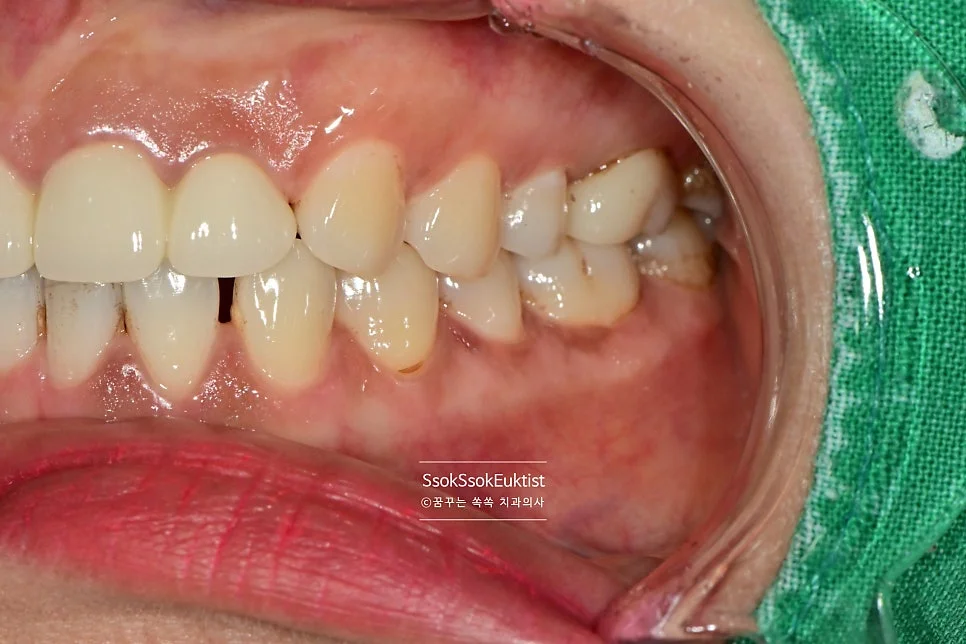

Case 3. 검은 착색 — 분사형 스케일러로 해결

착색 제거 케이스3 전 검은 착색

치아 표면의 검은색 착색 — 제거가 안된다며 찾아오신 분

치아 표면에 검은색 착색이 제거가 안된다며 찾아오신 분인데요. 분사형 스케일러를 이용해 스케일링뿐만 아니라 착색물질도 깨끗하게 제거해 봅니다!^^

착색 제거 케이스3 후 깨끗한 치아

착색 제거를 하기 위해서는 가루를 강한 수압으로 분사하는 분사형 스케일러가 필수입니다^^